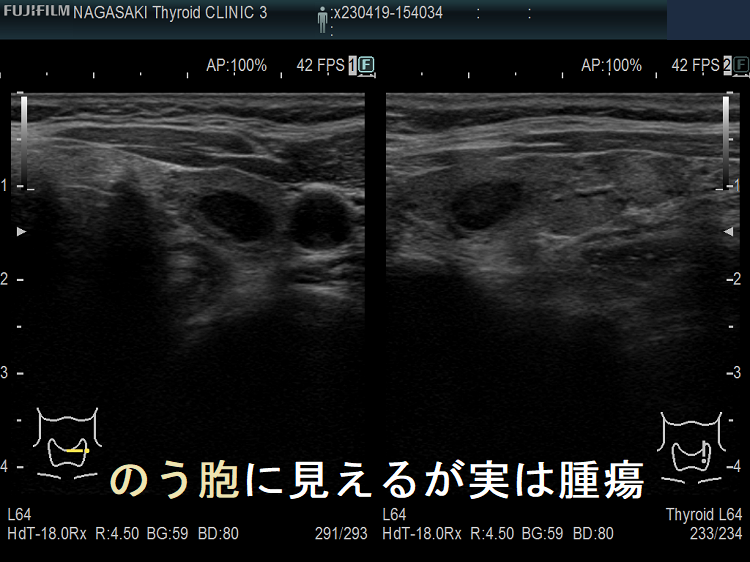

甲状腺のう胞に見えるが実は甲状腺腫瘍

甲状腺のう胞(甲状腺嚢胞)に見えるが甲状腺腫瘍 超音波(エコー)画像;低エコー(真っ黒)で、内部にコロイド様物質があるように見えるため、甲状腺のう胞(甲状腺嚢胞)と間違えます。

たとえば、通常Bモードでは、

1. のう胞(嚢胞)に見えても、高感度パワードプラーで低流速の細い血管が検出され、実は真っ黒な(極めて低エコーな)甲状腺腫瘍 [甲状腺のう胞(甲状腺嚢胞)に見えるが甲状腺腫瘍]

2. 充実性腫瘍に見えても、高感度パワードプラーで低流速の細い血管が検出されず、実はただの甲状腺のう胞腺腫(甲状腺嚢胞腺腫)(内部の不均質な実質様エコーは粘稠なコロイド物質)

だったなど、臨床診断が覆る場合があります。特に1.の場合は、甲状腺腫瘍甲状腺のう胞(甲状腺嚢胞)と間違えると大変な事になります。極めて低エコーな甲状腺腫瘍は、甲状腺乳頭癌甲状腺濾胞癌甲状腺髄様癌甲状腺悪性リンパ腫の可能性があるからです。

甲状腺のう胞(甲状腺嚢胞)に見えるが甲状腺腫瘍 超音波(エコー)画像;通常Bモードでは、低エコー(真っ黒)で、内部にコロイド様物質があるように見えて、甲状腺のう胞(甲状腺嚢胞)と間違えます。

甲状腺のう胞に見えるが実は甲状腺腫瘍 パワードプラー

高感度パワードプラーで低流速の細い血管が検出され、甲状腺腫瘍[濾胞性腫瘍]だった。